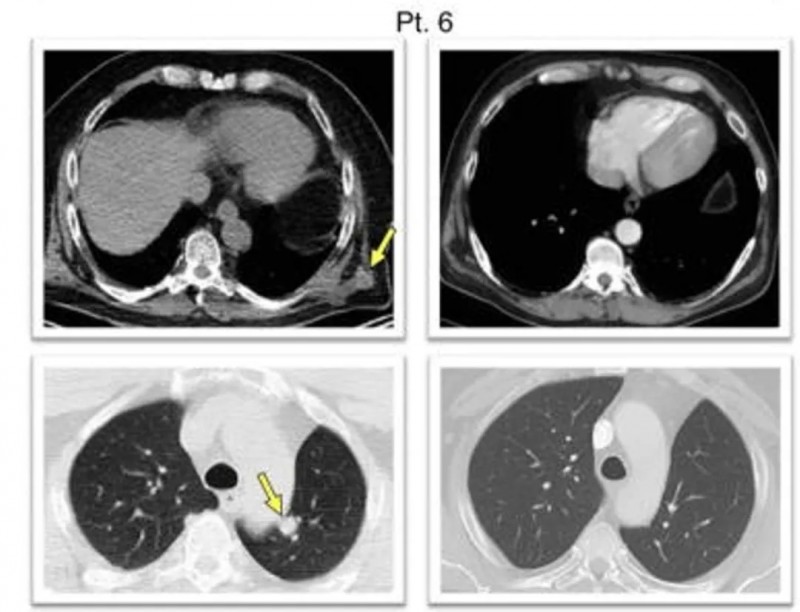

患者6:末次加强疫苗接种后1周的胸部CT扫描显示,左侧胸壁外侧及后外侧有多发软组织结节(左上图黄色箭头示2.1×1.8cm结节示例),且左下肺叶存在结节(左下图黄色箭头所示);16.5周后完成4剂帕博利珠单抗治疗,复查CT显示所有病灶完全消退,达到完全缓解标准。

▲图源“Nature”,版权归原作者所有,如无意中侵犯了知识产权,请联系我们删除